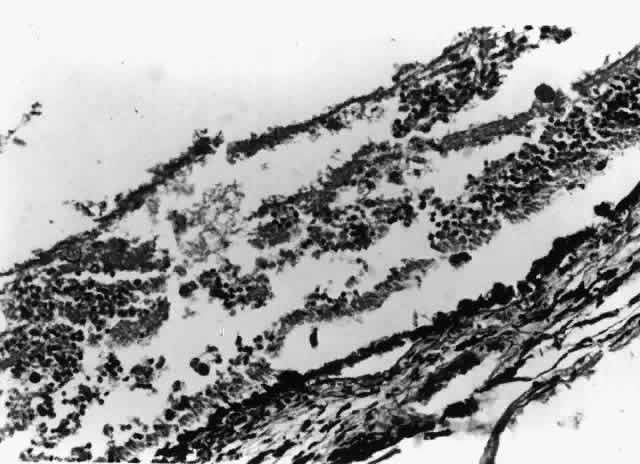

Nontuberculous mycobacterial infections can also produce choroidal granulomata, in which acid-fast bacilli can be found in histiocytes (Fig. 6). Mycobacterium avium complex is the most common cause. Infections have been reported most commonly as incidental findings at autopsy,9,17 although round, yellow-white lesions resembling choroidal pneumocystosis on fundus examination have been confirmed to be nontuberculous mycobacterial granulomata.31

Fig. 6. A focal choroidal granuloma underlying an area of cytomegalovirus retinopathy with exudative retinal detachment. The granuloma contained acid-fast bacilli (hematoxylin-eosin; original magnification × 125). (Photograph courtesy of Robert Y. Foos, MD)